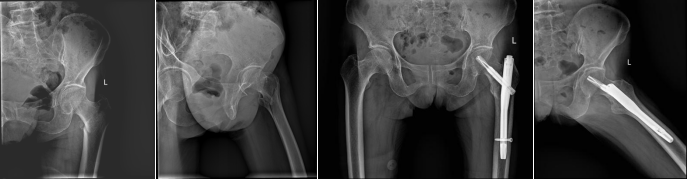

71岁张某(本院病例)左股骨粗隆间骨折合并冠心病,经心内科、呼吸科、神经内科、麻醉科联合会诊,采用闭合复位微创技术完成PFNA内固定术,术中出血量控制在50ml以内,术后第2日即进行功能康复训练。